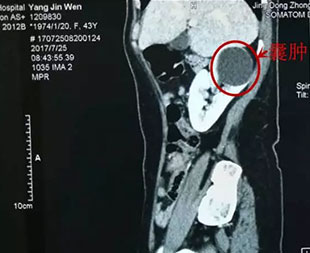

泌尿外科主要治疗范围有:各种尿结石和复杂性肾结石;肾脏和膀胱肿瘤;前列腺增生和前列腺炎;睾丸附睾的炎症和肿瘤;睾丸精索鞘膜积液;各种泌尿系损伤;泌尿系先天性畸形如尿道下裂、隐睾、肾盂输尿管连接部狭窄所导致的肾积水等等。